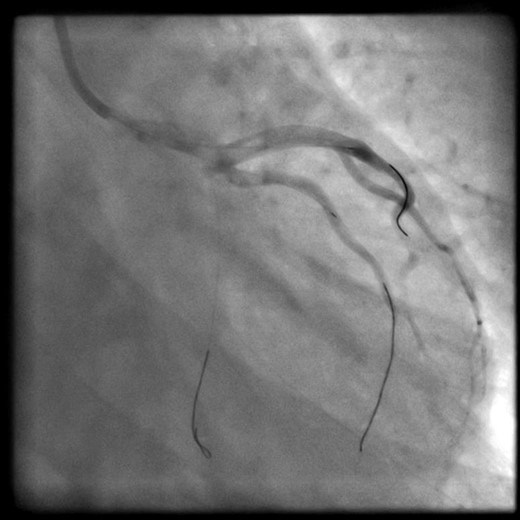

The patient acutely became hemodynamically unstable and suffered a cardiac arrest. Cardiopulmonary resuscitation was started and the patient was intubated. Return of spontaneous circulation (ROSC) was achieved with inotropes, vasopressors and intra-aortic balloon counterpulsation. Following ROSC, angiographic wires were passed into the coronaries. However, the operator was unable to wire the true lumen of the circumflex artery (Fig. 2).

Wires left into the coronaries during transfer. LAD and intermediate: true lumen successfully wired. Cx: unable to wire true lumen.

At this point, decision was made to transfer the patient to our cardiothoracic unit for emergency coronary artery bypass graft. The patient was transferred to our unit with the angiographic wires left on purpose into the coronaries.